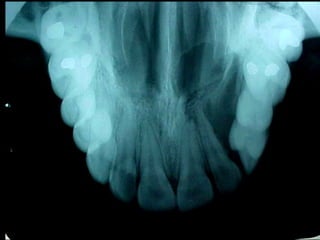

Odontoma compuesto

2 cms.

Queratoquiste odontogénico

Otro caso